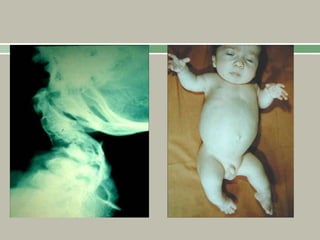

1, 2: Odontoid

hypoplasia and subtle anatomic axis

instability.

4:Pelvis, delayed ossification and irregular

epiphyses of the hips with overgrown

trochanters.

Fairbank’s triangle is present

3,5: Kyphoscoliosis with irregular vertebral

epiphyses.

Platyspondyly (flattened vertebral bodies) is

evident in lumbar spine